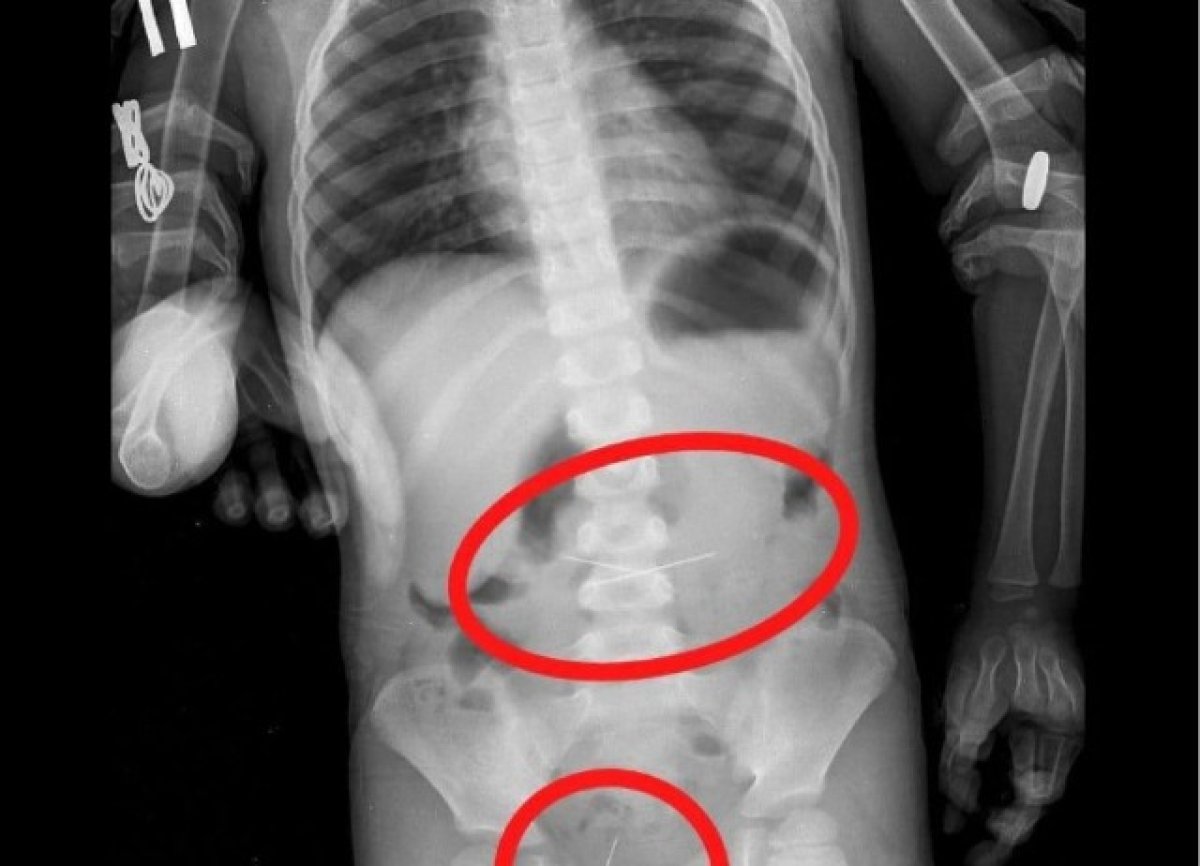

Дәрігерлер бірнеше тігін инесін жұтып қойған үш жасар баланың өмірін сақтап қалды. Жамбыл облысы денсаулық сақтау басқармасының баспасөз қызметінен хабарлағандай, бүлдіршіннің анасы Жамбыл облыстық көпсалалы балалар ауруханасының қабылдау бөлмесіне осындай шағыммен келген. Рентгенге түсіру нәтижесінде асқазаннан екі тігін инесі табылды. Дәрігерлер инені алып тастаған. Бала бақылауда болды. Үшінші инені мамандар жамбастан тапты. Ол да сәтті алынған. «Қазір бүлдіршін үйінде. Өзін жақсы сезінеді»,-дейді.